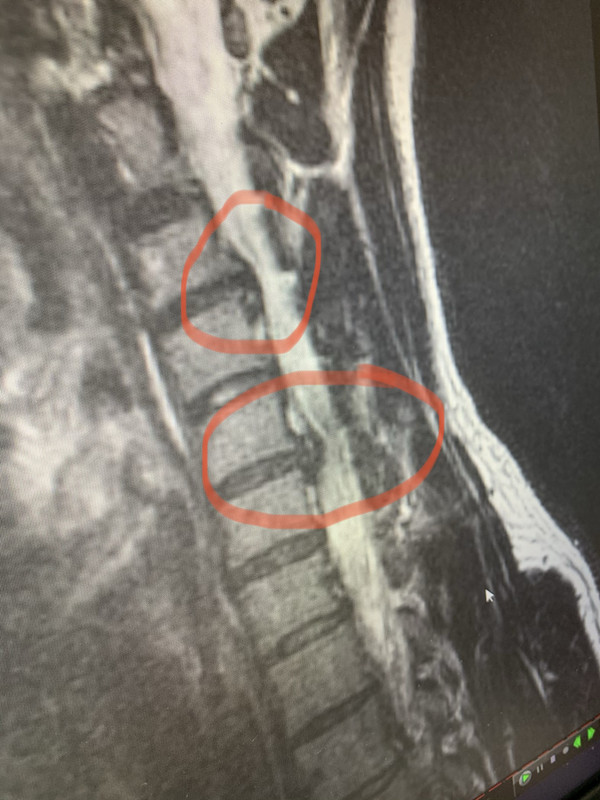

Herniated Disc

I’m 29 years old and I’ve got two herniated disk in neck. Has anyone had replacement surgery, injections, etc. on these? I will be getting a few opinions from orthopedist before making a decision. Thanks!

I think it has been a thing for years, but I messed it up again about a month ago while lifting. Had 24/7 pain for 3 weeks even with treatment, got MRI last week and results yesterday.

quote:There is no such thing as microdiscectomy in the cervical spine. For cervical spine surgery you can have an ACDF (anterior discectomy and fusion) or an artificial disc replacement surgery.

I would try the microdiscectomy before doing the replacement procedure. It’s much less invasive and doesn’t require any hardware to be installed. I have mine scheduled for the 11th of Februar

To the OP, the lower level disc herniation is pretty significant and will probably require surgery. The question is will the upper level also need to be done. And if so then you would probably have to fuse the level in between them resulting in a 3 level fusion.

On the positive side, most people do very well after having a neck fusion. Peyton Manning play a few more years in the NFL after a one level.